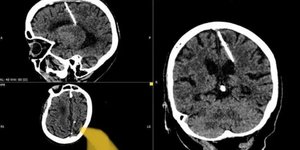

Πάτρα: Χειρούργησαν άνδρα και ξέχασαν στην κοιλιά του μια βελόνα!